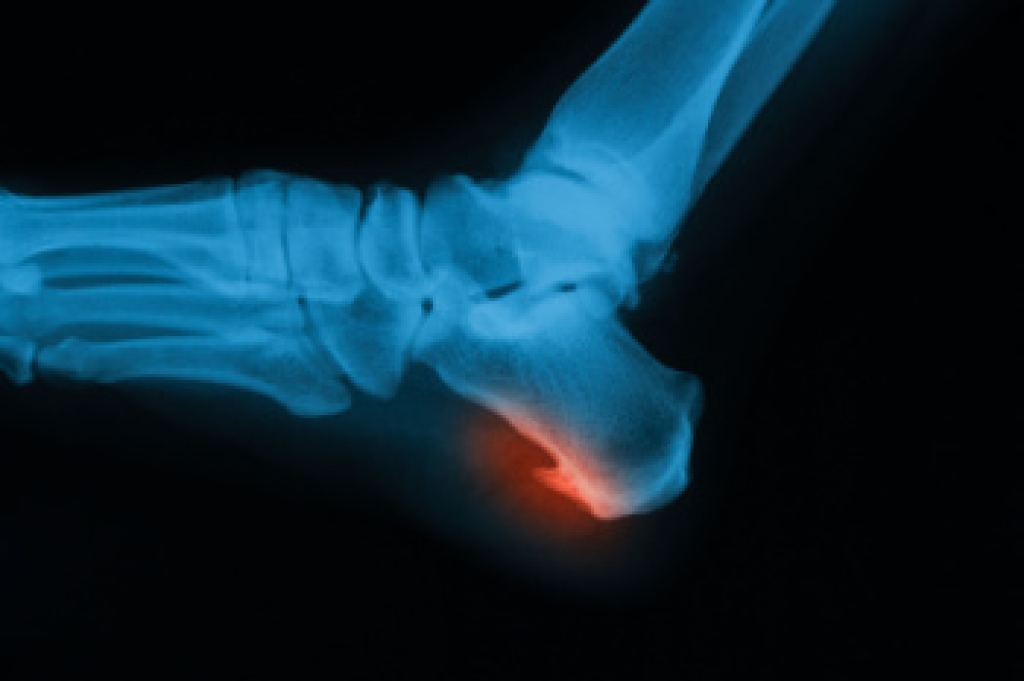

Heel spurs are formed by calcium deposits on the back of the foot where the heel is. This can also be caused by small fragments of bone breaking off one section of the foot, attaching onto the back of the foot. Heel spurs can also be bone growth on the back of the foot and may grow in the direction of the arch of the foot.

A heel spur is a bony growth that often develops on the underside of the heel bone due to calcium deposits forming over time. It often occurs as a result of repeated strain on foot muscles and ligaments. Causes include aging, joint stress, and being overweight. Poorly fitting footwear and participating in high impact athletic activity also may contribute. Risk factors involve prolonged standing, flat feet or high arches, and improper support during movement. Symptoms include sharp heel pain, especially with the first steps after rest, and ongoing discomfort while walking. A podiatrist can diagnose heel spurs through an examination and imaging. Treatment options include custom orthotics, stretching exercises, and supportive footwear. If you have heel pain, it is suggested that you consult a podiatrist who can accurately diagnose and treat heel spurs.